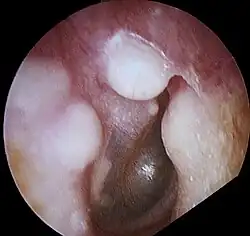

| Osteoma of external auditory meatus | |